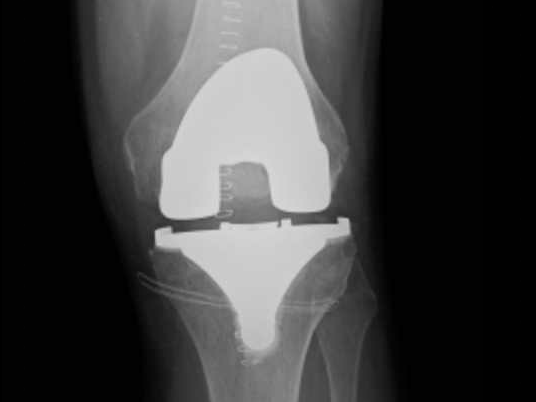

Les composants d'une Prothèse Totale de Genou

Cette intervention consiste à remplacer l’articulation du genou par des composants artificiels qui reproduisent l’anatomie initiale du genou. Le type d’implant doit être adapté à chaque cas particulier, en ce qui concerne sa forme, sa taille, la nature des matériaux entrant dans sa composition, son revêtement extérieur et la technique chirurgicale à employer.

Généralement, une prothèse de genou se divise en trois parties : un insert fémoral, une embase tibiale surmontée d’un polyéthylène et un resurfaçage de la rotule par un polyéthylène. Les composants sont le plus souvent fixés par du ciment.

La prothèse que nous mettons en place est un implant en alliage CrCoMo (implant fémoral) et titanium (implant tibial).